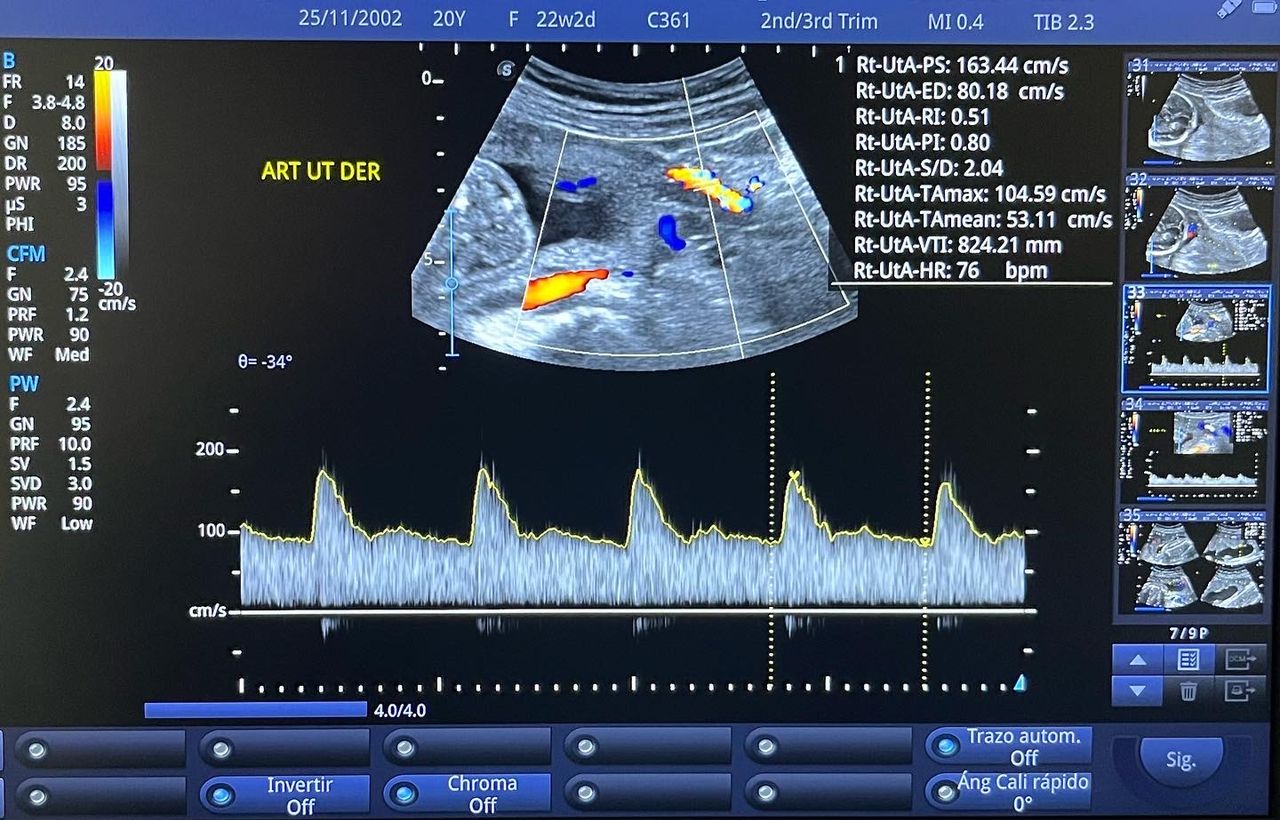

Médico general con 15 años de experiencia, master en enfermedades infecciosas y antibioticoterapia por parte de la Universidad Cardenal Herrera en Valencia, ademas de diversos diplomados en el área de Infectología y Parasitología, Urgencias, Imagenología y Medicina del Trabajo. He laborado en Hospitales y Clínicas en el área de Urgencias, en Laboratorios realizando estudios de Imagen, en especifico ultrasonidos de todo tipo desde básicos hasta avanzados incluidos los obstétricos estructurales, en Secretaría de Salud del Estado de Querétaro realizando ultrasonidos obstétricos para la detección de malformaciones en los tres trimestres del embarazo en diversos centros de salud, como médico de Empresas en el campo de Salud Laboral y actualmente en este consultorio en donde para su mejor atención y siempre buscando integrar la mayoría de las herramientas diagnosticas cuento con equipo de ultrasonido como apoyo en la exploración del paciente o como servicio diagnostico por imagen, realizo ultrasonidos convencionales (hepatobiliar (hígado, páncreas, vesícula y bazo), vías urinarias, ginecológico abdominal y transvaginal, tiroideo, prostático, testicular, pared abdominal) y especializados (dopler obstétrico en los 3 trimestres de embarazo), musculoesquelético en lesiones deportivas. También cuento con un equipo de electrocardiograma de 12 derivaciones para monitoreo completo del funcionamiento cardiaco, espirometria para evaluar la función pulmonar en la consulta, pruebas rápidas que se realizan en consultorio para detectar de forma mas precisa enfermedades infecciosas como Influenza A y B, covid19, infecciones urinarias, dengue, zika, chikungunya. Cuento con diversas vacunas para prevención de enfermedades. Siempre con el objetivo de dar el mejor servicio y atención a su salud. Lo espero en consulta para escucharlo y estudiar su caso de la forma más completa posible, estoy seguro de que tendremos las mejores opciones para su tratamiento. Mi tranquilidad es que usted se vaya con todas sus preguntas e inquietudes resueltas.

• Ultrasonido obstétrico